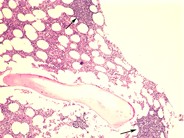

CLL – nodular pattern - 1.

Category: Lymphoma: Mature B-cell and Plasma cell Neoplasms > Low-grade B-cell lymphoma > Chronic Lymphocytic Leukemia/Small Lymphocytic Lymphoma

Discreet nodules (arrows) of small lymphoid cells in the biopsy can be appreciated under low power.